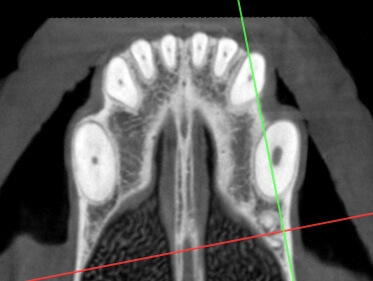

CT Imaging showed:

T/NV (non vital tooth) 204.

Below: Discolored tooth on CT Imaging

%20-%20March%202024/CT%20Image%20of%20discolored%20204.jpg?width=285&height=412&name=CT%20Image%20of%20discolored%20204.jpg)

%20-%20March%202024/CT%20Image%20comparing%20upper%20canines%20root%20canals%20104%20vs%20discolored%20204.jpg?width=373&height=281&name=CT%20Image%20comparing%20upper%20canines%20root%20canals%20104%20vs%20discolored%20204.jpg)